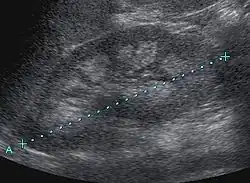

| Bilateral nephrocalcinosis seen on an abdominal x-ray | |

Nephrocalcinosis is diagnosed for the most part by imaging techniques. The imagings used are ultrasound (US), abdominal plain film and CT imaging.[10] Of the 3 techniques CT and US are the preferred modalities.